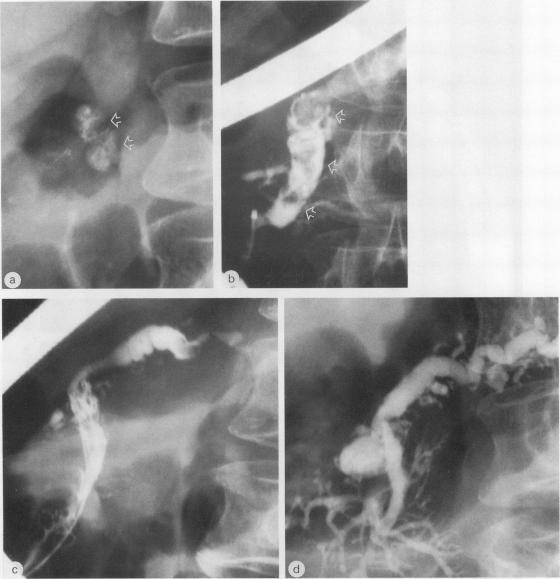

Extracorporeal shock wave lithotripsy of pancreatic stones was performed in eight patients with chronic pancreatitis and a dilated duct system harbouring stones 5 to 20 mm (means 10 (SD) 5 mm) in diameter. After endoscopic sphincterotomy of the pancreatic orifice the stones were disintegrated by shock waves under fluoroscopic control using a kidney lithotripter (Dornier HM3). The procedure was well tolerated by all but one patient, who had a mild pancreatitic attack immediately after lithotripsy. Clearance of the pancreatic duct systems from the larger stones was achieved in seven of eight patients. Half of the patients showed no improvement in the intensity and frequency of pain. The other patients had a marked amelioration of symptoms, however, both immediately and during a mean follow up interval of 11 (eight) months. A selective combined approach by endoscopy and extracorporeal shock wave lithotripsy for the treatment of pancreatic stones seems promising.

对8例慢性胰腺炎且伴有直径5至20毫米(平均10(标准差)5毫米)结石的扩张导管系统患者进行了体外冲击波碎石术治疗胰腺结石。在胰腺开口进行内镜括约肌切开术后,使用肾脏碎石机(多尼尔HM3)在荧光镜控制下通过冲击波将结石粉碎。除1例患者在碎石术后立即发生轻度胰腺炎发作外,所有患者对该手术耐受性良好。8例患者中有7例较大结石从胰管系统清除。一半患者的疼痛强度和频率没有改善。然而,其他患者无论是在术后即刻还是在平均11(8)个月的随访期内症状都有明显改善。内镜检查和体外冲击波碎石术联合治疗胰腺结石的选择性联合方法似乎很有前景。